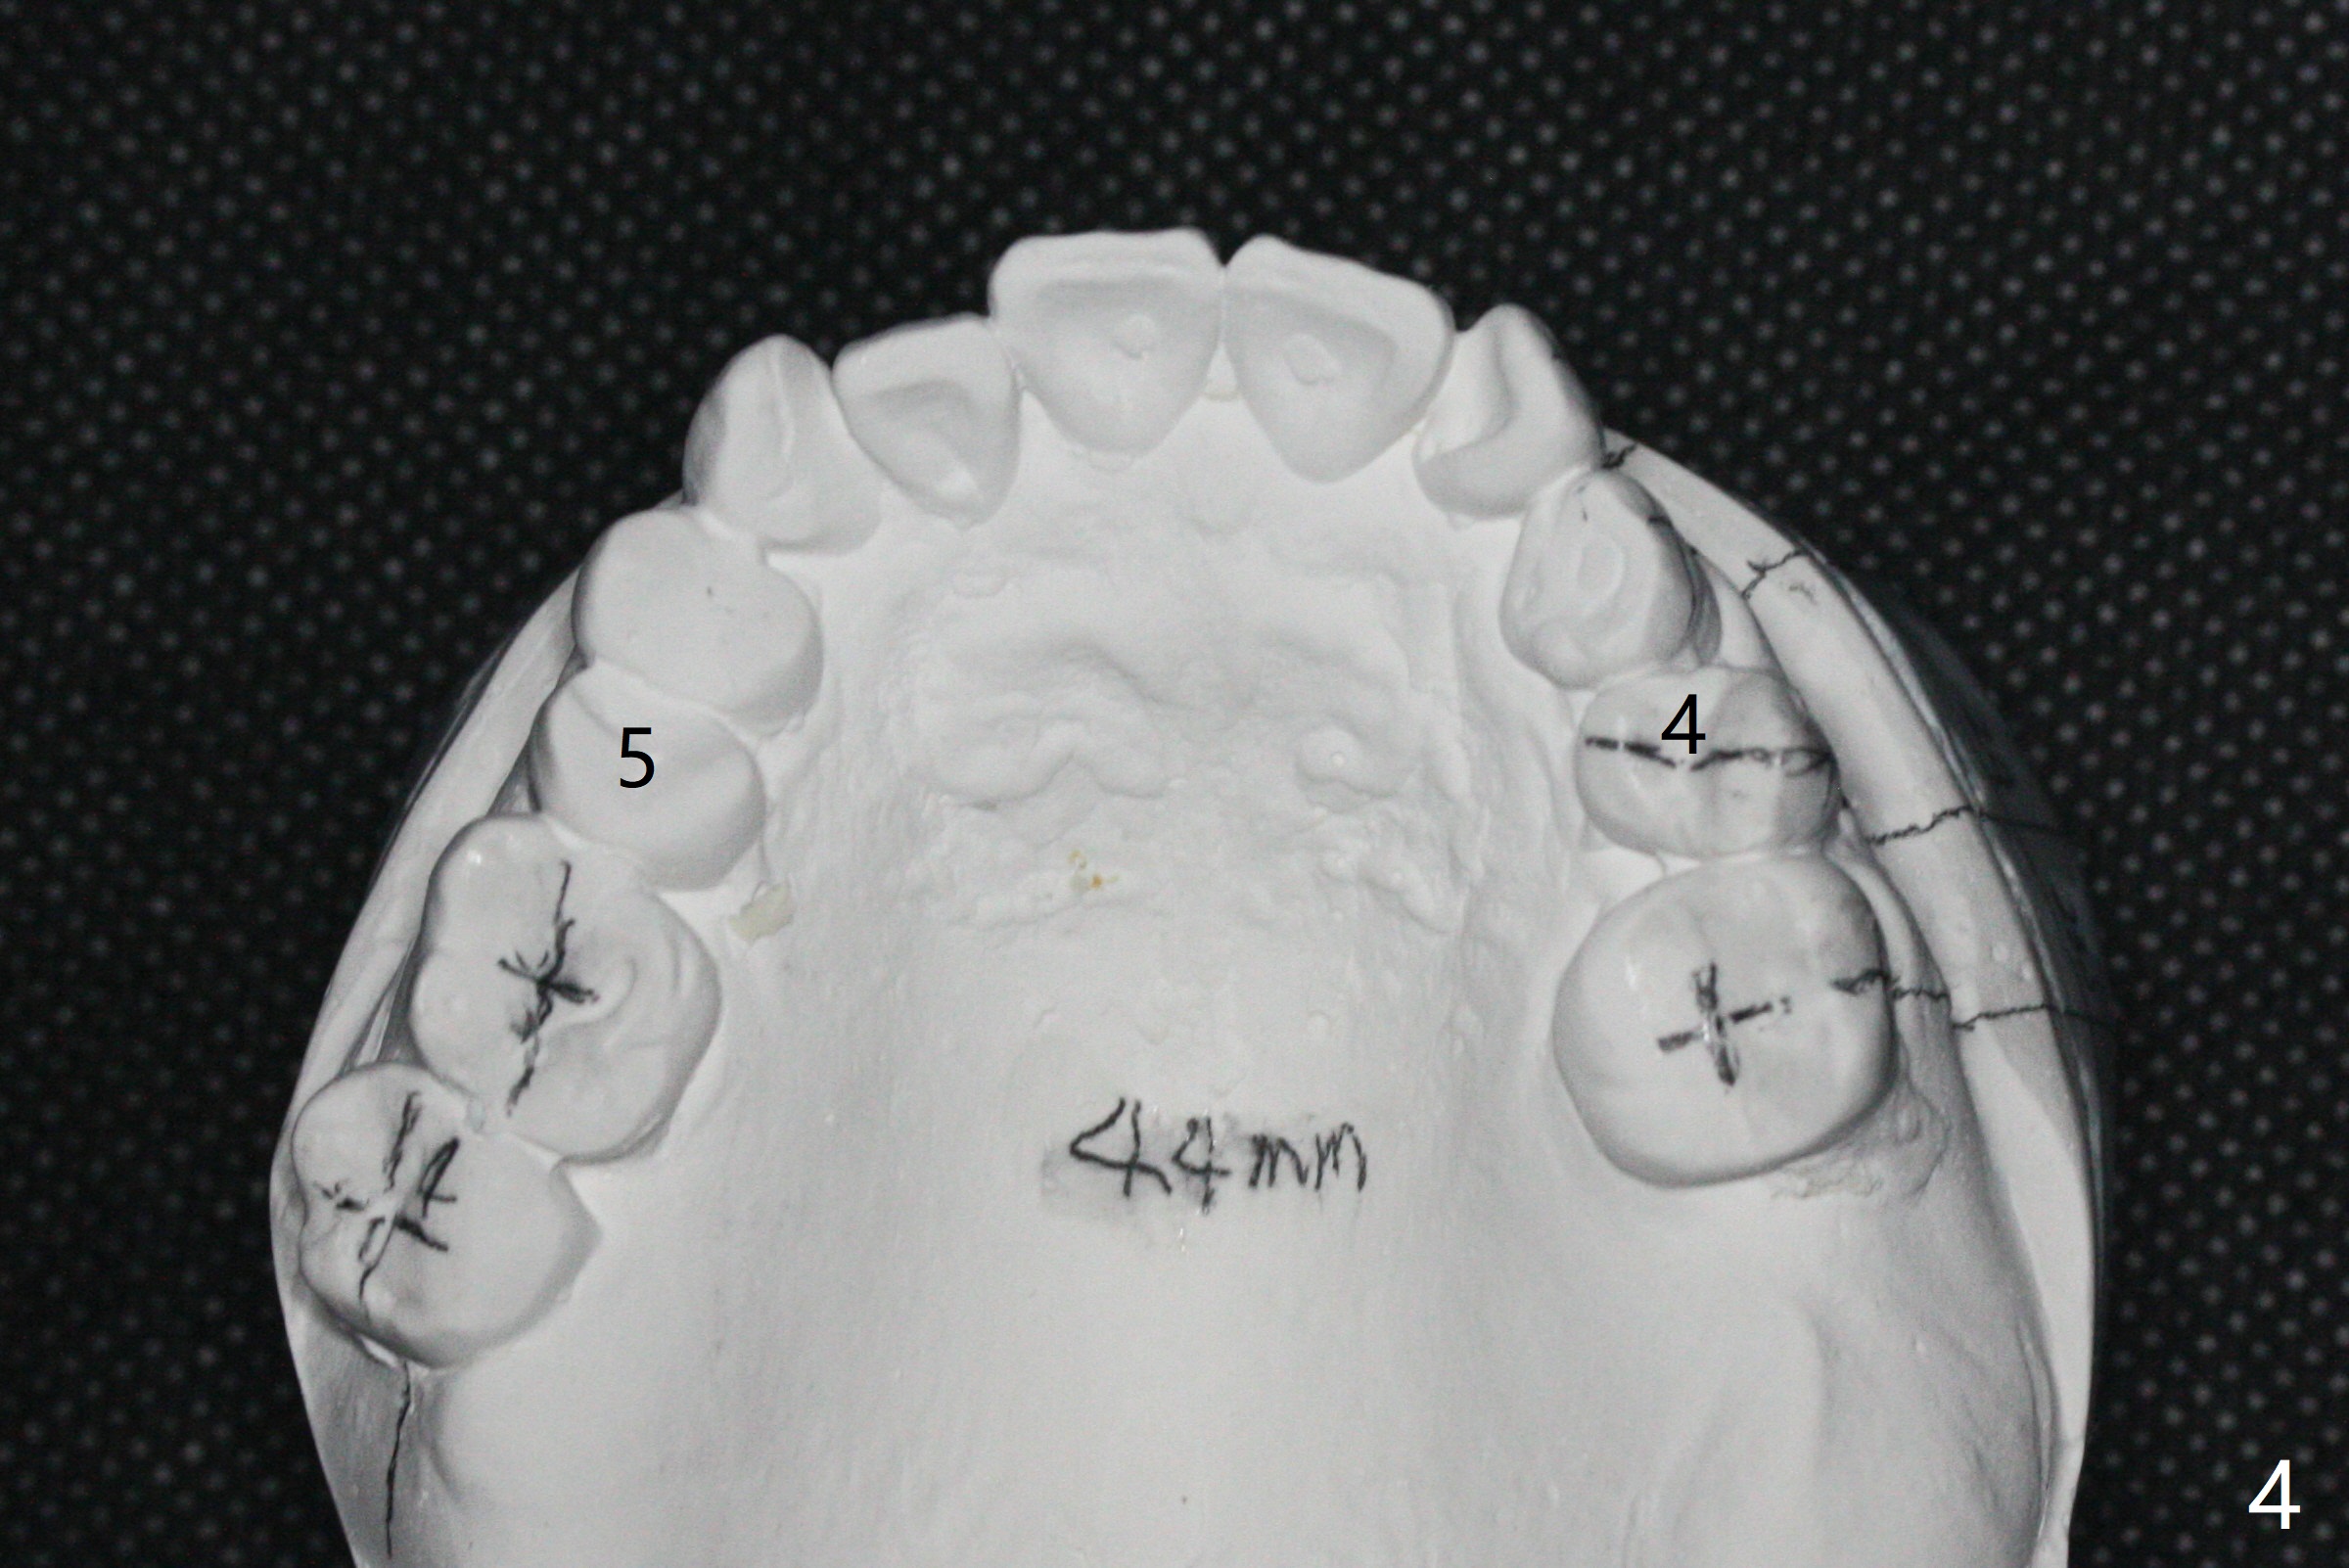

A 54-year-old man remains difficult in mastication in spite of implant placement at #14 and 31 (Fig. A, B, E, including screw loosening (poor trajectory at #14)). In addition to 2 more implants at #15 and 18 with guide, malocclusion seems to be necessary to be addressed (Fig.1-5). It appears that UR, LL4 should be extracted for orthodontic treatment (Fig.6-10). To reduce screw loosening, IS guide will be used to place IBS (5x9mm) and tissue-level (5x11mm) implants at #15 (PRF)and 18, respectively. If the one at #14 or 15 keeps loosening, splint #14 and 15 crowns. In fact the patient agrees with limited ortho (UR7 cross bite).